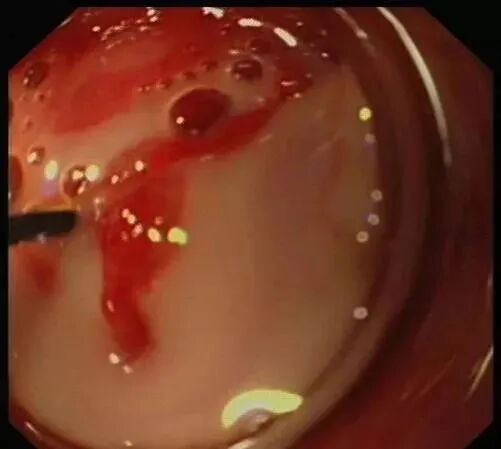

(下图可见白色脓液)

当黄斑马导丝及导管置入阑尾腔时,可见脓性分泌物涌出。随之进行阑尾腔冲洗;